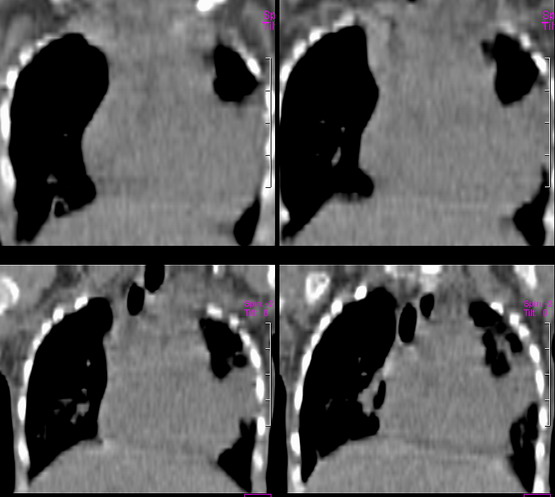

患儿 六月 咳嗽,反复发热二周,加重伴气喘3天

左肺呈大片状实变影,密度欠均匀,边界模糊,残存正常的肺组织呈气肿表现,右肺内可见磨玻璃样改变,如此年幼的婴儿首先考虑左肺发育不良并继发感染可能性大

左肺呈大片状实变影,密度欠均匀,边界模糊,残存正常的肺组织呈气肿表现,右肺内可见磨玻璃样改变,考虑左肺发育不良并继发感染可能性大.图象太小

此患儿于前日死亡,病检结果:

左肺发育不良伴感染.